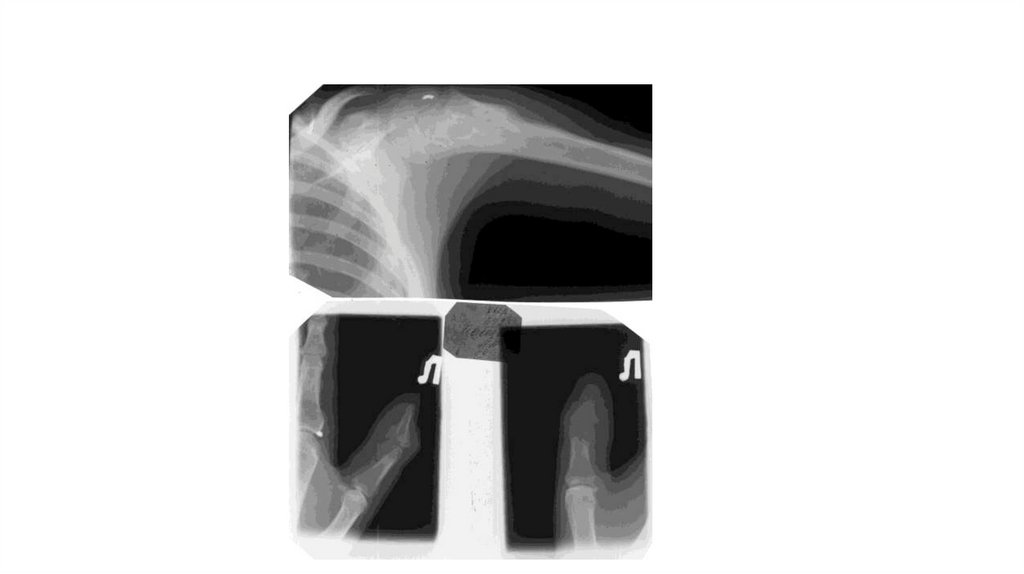

«Воспалительные

заболевания опорнодвигательного аппарата»